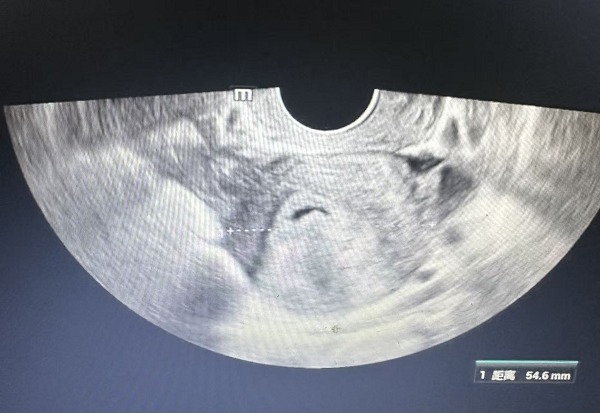

宫腔镜下子宫黏膜下肌瘤冷刀切除术:李媛副主任医师、周丽萍副主任医师组成的妇科团队,为一名45岁宫腔占位女性患者成功实施宫腔镜下子宫黏膜下肌瘤冷刀切除术。患者术前超声提示宫腔内4.4×1.9cm高回声占位,术后病理确诊为黏膜下平滑肌瘤。该技术经女性自然腔道操作,全程直视下以机械方式精准切除肌瘤,无电切、无热损伤,最大程度保护子宫内膜完整性。手术出血少、创伤微,患者术后疼痛轻、恢复快、住院时间短,充分体现现代妇科“微创、安全、高效、保器官”的诊疗理念。